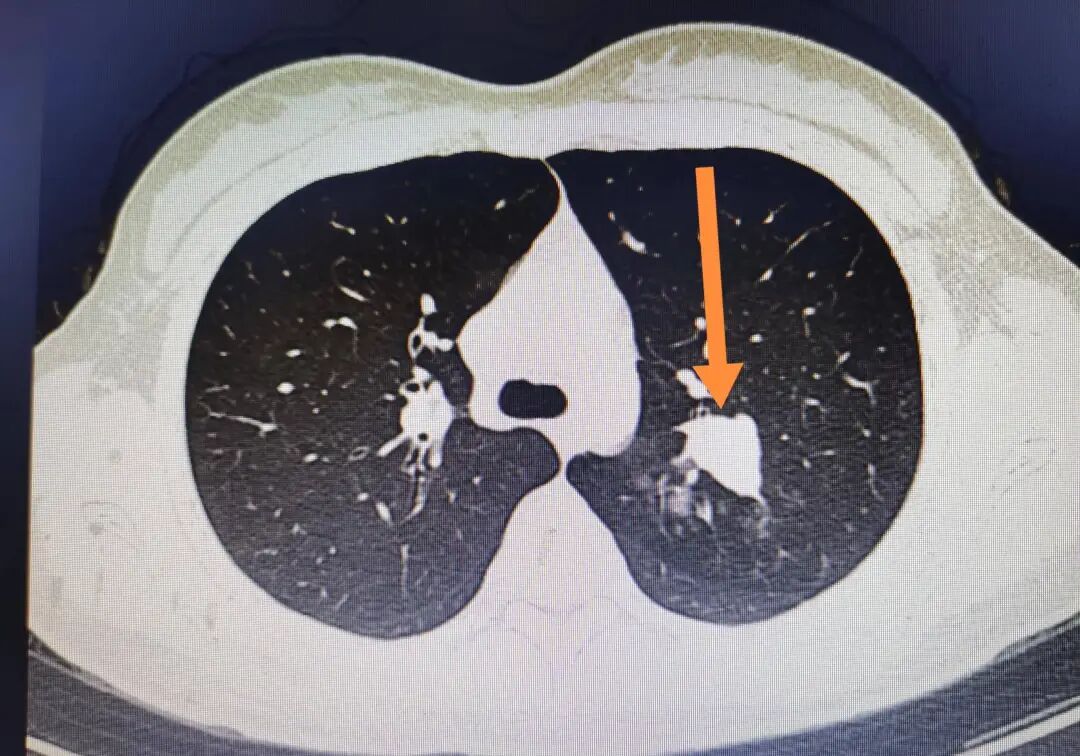

这位患者虽然年纪大了,但他没有吸烟等不良习惯,这是非常难得的。体检中发现了肺部有占位性病变,并及时进行了手术治疗。

其次“中央型”是指肿瘤的生长位置。中央型肺癌通常生长在肺门附近,这个区域布满了重要的血管和神经,是呼吸系统的核心地带。

由于这个位置特殊,中央型肺癌在生长过程中更容易侵犯到这些重要的结构,导致一系列严重的并发症。此外,由于手术难度较大中央型肺癌的治愈率相对较低,这也使得它成为了一种更为严重的肺癌类型。